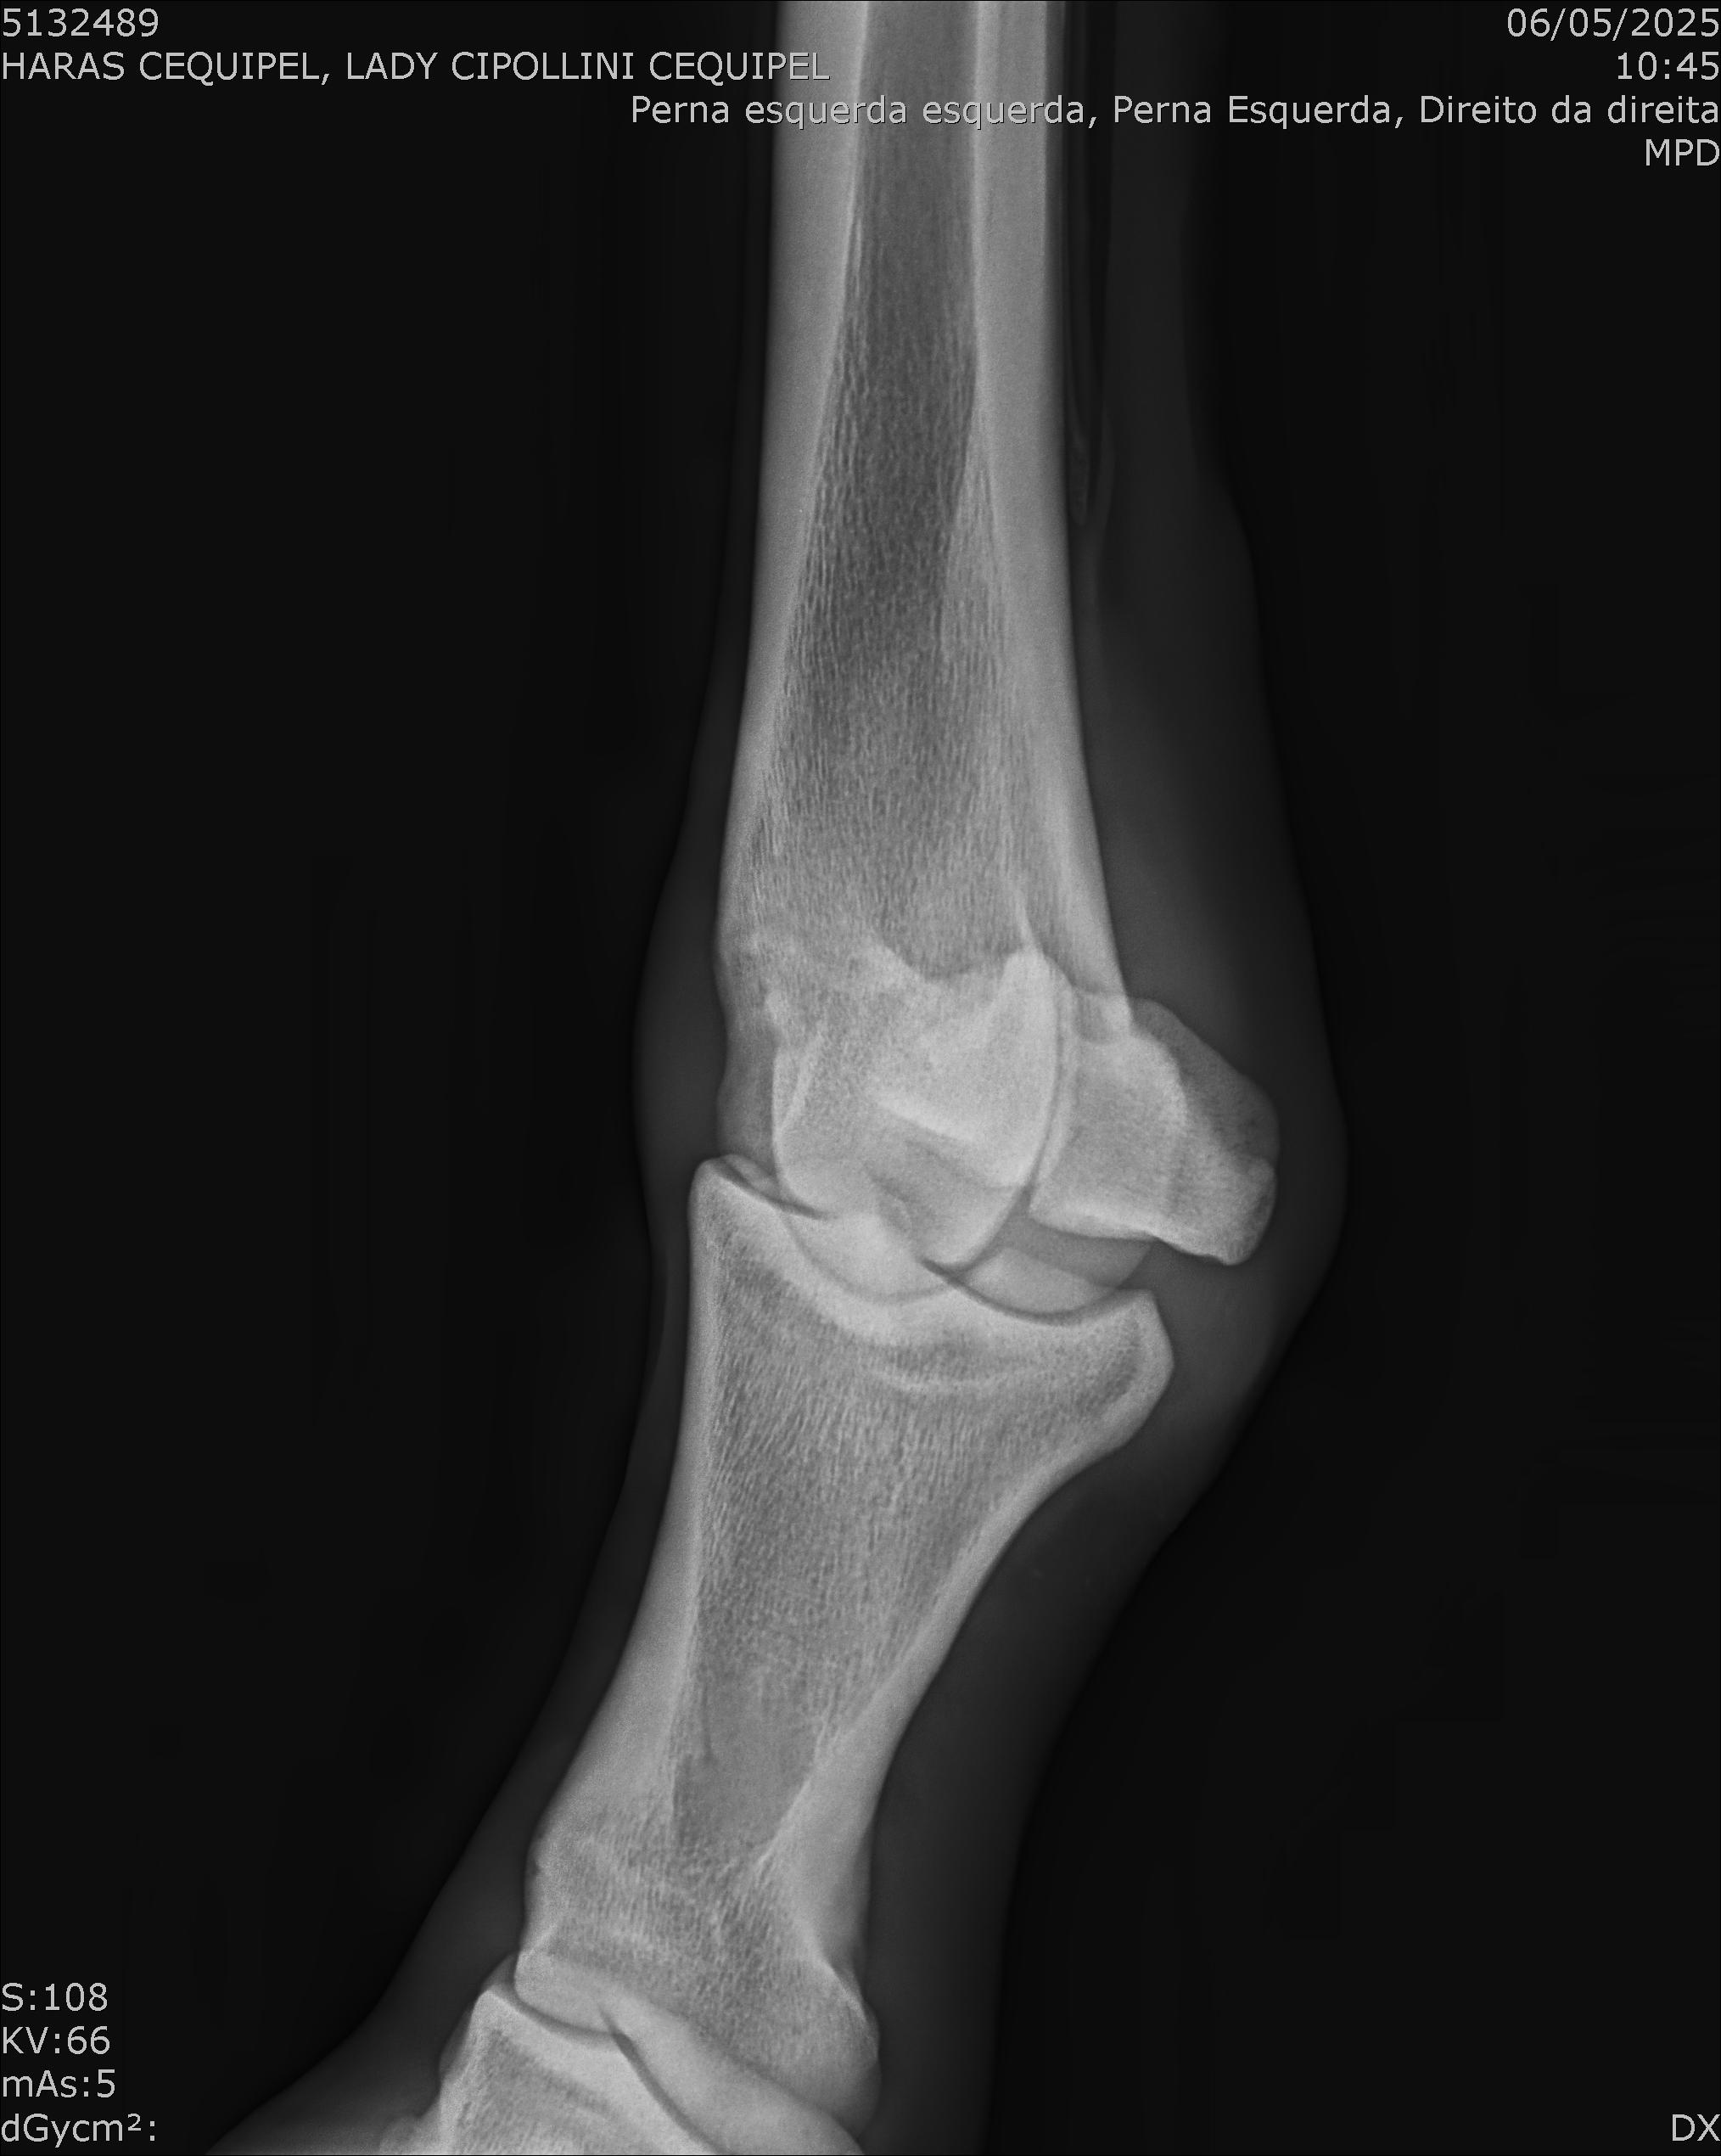

:: RAIOS-X DO LOTE